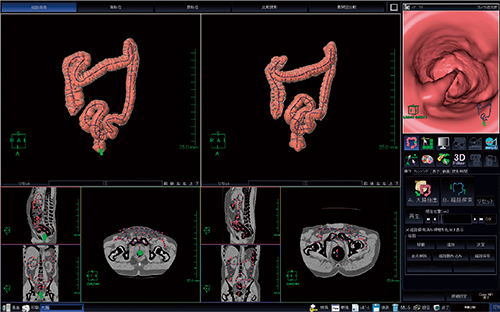

当院の大腸内視鏡検査では痛みが強く,下行結腸途中までの検査になってしまったが,S状結腸にType2の進行がんを思わせる隆起性病変(図5)が認められ,下行結腸途中から全周性の発赤で易出血性であった。大腸内視鏡検査より潰瘍性大腸炎を発生母地としたcolitic cancerを疑い,下行結腸から口側の大腸と血管分岐の情報を得るためにCT angiographyを含めた大腸CT検査が行われた。

図5 大腸内視鏡画像

大腸CT検査では,上行結腸から下行結腸途中にかけての粗造な粘膜変化と壁の肥厚,S状結腸に中心陥凹の隆起性病変が認められた。粘膜の変化は上行結腸途中まで見られ,盲腸部は正常と思われた。また,隆起性病変付近のS状結腸は,潰瘍性大腸炎の特徴の一つであるハウストラの消失(鉛管像)が見られた(図6)。

図6 Colitic cancerが疑われた患者の大腸CT検査

a:仮想内視鏡画像 b:アキシャル画像 c:コロナル画像

d:仮想注腸画像(→隆起性病変) e:仮想注腸画像(腹臥位)。

隆起性病変付近の鉛管像と,上行結腸から下行結腸の粘膜変化が見られる。

手術は腹腔鏡補助下で上行結腸からS状結腸の切除予定であったが,術中に盲腸に至る潰瘍性大腸炎の変化が認められ,拡大右半結腸切除術(回腸S状結腸吻合)が行われた。術後の病理検査では,早期がんと同部位の潰瘍性大腸炎と診断された。

本症例では,大腸内視鏡挿入困難な潰瘍性大腸炎患者に対して大腸CT検査を行うことで範囲を知る目的があったが,中等度(粘膜粗造など)の変化を有する部位は判別できたものの,軽度の変化までは判別困難であった。CT angiography(図7)では,S状結腸動脈分岐と静脈との位置関係の情報を得ることができ有用であった。

図7 CT angiography(仰臥位)